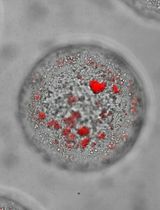

Cover of The Journal of Biological Chemistry, featuring study using the protocol.